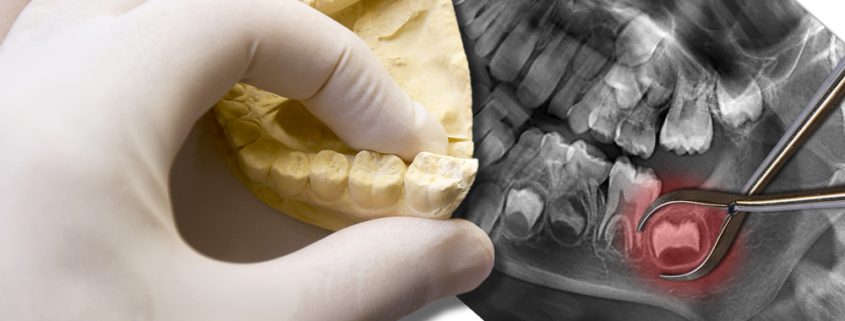

Maux de tête : pensez aux dents de sagesse !

Vous souffrez de maux de tête inexpliqués ? Et si vos dents de sagesse étaient en train de pousser ? Bien qu’il ne soit pas toujours facile de trouver l’origine d’un mal de tête récurrent, cette hypothèse devrait être envisagée sérieusement ! Découvrez comment les dents de sagesse peuvent entraîner des douleurs et pourquoi il est préférable de … Lire la suite de Maux de tête : pensez aux dents de sagesse !